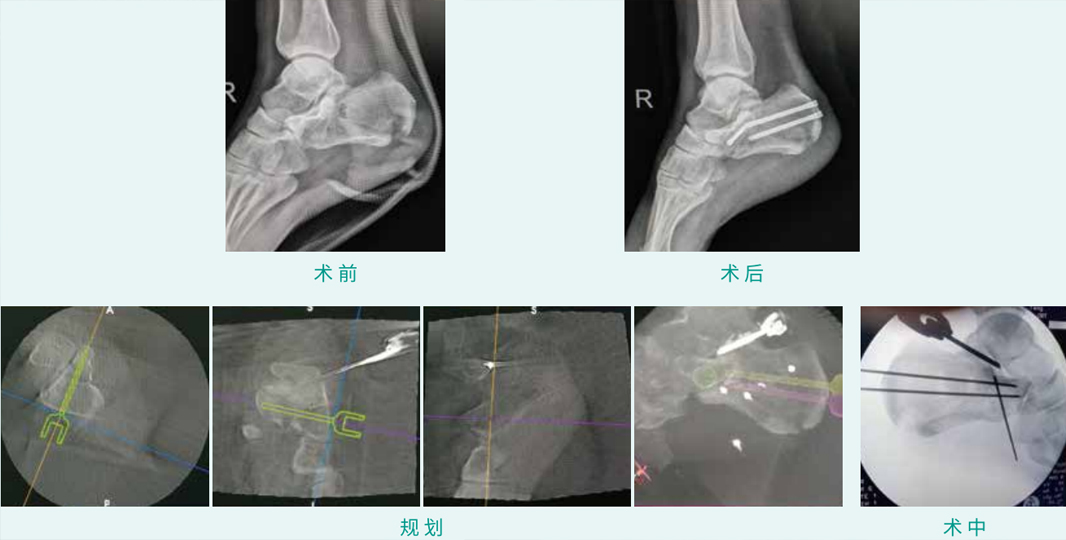

TiRobot ? Calcaneus Fracture Percutaneous Screw Fixation

天玑? 辅助跟骨骨折经皮空心螺钉内牢靠术

基本情形:患者男,,,,,,,27岁,,,,,,,跟骨骨折

机械人累积用时:30分钟

植入物:3枚空心螺钉

病例泉源:四川省人民医院 张斌 唐智